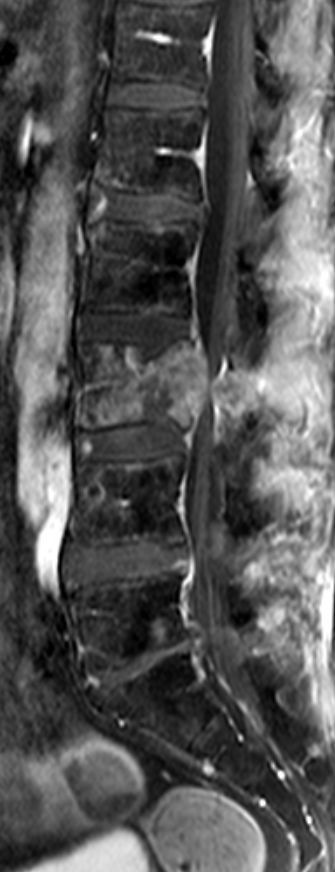

| 14% regionale Lymphknoten, 31% Lunge, 15% Knochen | MRT: Knochenmetastasen

![]() | ||